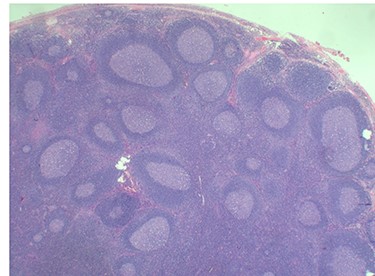

Because of the recent increase in the size of the swelling, the patient presented to our clinic and agreed to undergo excision of the swelling. A well-circumscribed swelling measuring 2.5 cm × 1.5 cm which was soft to firm in consistency was completely excised (Fig. 1). Histopathological examination showed sections of lymph node with florid follicular and germinal center hyperplasia (Fig. 2), and paracortical expansion by plasma cells, small lymphocytes and mast cells (Fig. 3). Marked eosinophilic infiltration with focal micro-abscess formation was present (Fig. 4). The features were consistent with Kimura’s disease. There was no evidence of malignancy. At 6 months follow-up, the patient had no evidence of recurrence.

Histopathology of the lymph node showing follicular and germinal center hyperplasia. Haematoxylin and Eosin stain. Magnification ×1.2.